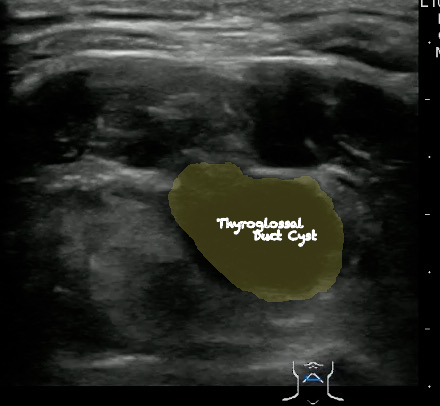

Thyroglossal duct cyst26

- Thyroglossal duct cysts typically related to hyoid bone:

- Often midline

- 25%-suprahyoid-submental region

- 75%-Infrahyoid or at the level of hyoid

- Variable sonographic appearance:

- Well-circumscribed anechoic cyst

- Increased through transmission

- Hypoechoic with internal debris

- No internal vascularity

- Heterogeneous pattern seen in repeated infections and hemorrhage due to prior aspirations

- Pseudo-solid echogenic appearance from proteinaceous contents secreted by epithelial lining

- Figure 34 and 35. Thyroglossal Duct Cyst

Video 22. Thyroglossal Duct Cyst